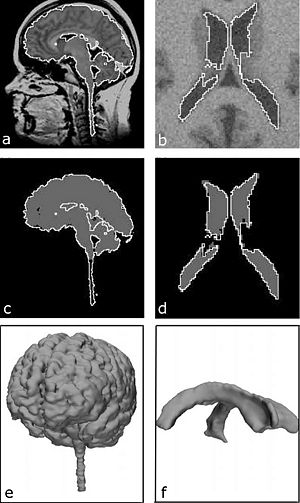

Publication: PLoS One. 2015 Dec 3;10(12):e0143821. PMID: 26633302 | PDF Authors: Gutierrez S, Descamps B, Vanhove C. Institution: Medical Image and Signal Processing Group, Ghent University-iMinds Medical IT department, Ghent, Belgium. Background/Purpose: Computed tomography (CT) is the standard imaging modality in radiation therapy treatment planning (RTP). However, magnetic resonance (MR) imaging provides superior soft tissue contrast, increasing the precision of target volume selection. We present MR-only based RTP for a rat brain on a small animal radiation research platform (SARRP) using probabilistic voxel classification with multiple MR sequences. Six rat heads were imaged, each with one CT and five MR sequences. The MR sequences were: T1-weighted, T2-weighted, zero-echo time (ZTE), and two ultra-short echo time sequences with 20 μs (UTE1) and 2 ms (UTE2) echo times. CT data were manually segmented into air, soft tissue, and bone to obtain the RTP reference. Bias field corrected MR images were automatically segmented into the same tissue classes using a fuzzy c-means segmentation algorithm with multiple images as input. Similarities between segmented CT and automatic segmented MR (ASMR) images were evaluated using Dice coefficient. Three ASMR images with high similarity index were used for further RTP. Three beam arrangements were investigated. Dose distributions were compared by analysing dose volume histograms. The highest Dice coefficients were obtained for the ZTE-UTE2 combination and for the T1-UTE1-T2 combination when ZTE was unavailable. Both combinations, along with UTE1-UTE2, often used to generate ASMR images, were used for further RTP. Using 1 beam, MR based RTP underestimated the dose to be delivered to the target (range: 1.4%-7.6%). When more complex beam configurations were used, the calculated dose using the ZTE-UTE2 combination was the most accurate, with 0.7% deviation from CT, compared to 0.8% for T1-UTE1-T2 and 1.7% for UTE1-UTE2. The presented MR-only based workflow for RTP on a SARRP enables both accurate organ delineation and dose calculations using multiple MR sequences. This method can be useful in longitudinal studies where CT's cumulative radiation dose might contribute to the total dose. |

Illustration of a CB-CT and five MR images of the same animal. a) Coronal CB-CT image and (b)-(f) biased field corrected and masked coronal MR images using a T1-weighted (b), T2-weighted (c), ZTE (d), UTE1 (e) and UTE2 (f) sequence. All CB-CT images were first co-registered using 3D Slicer version 3.6.3 by rigid body transformations using normalized mutual information. |